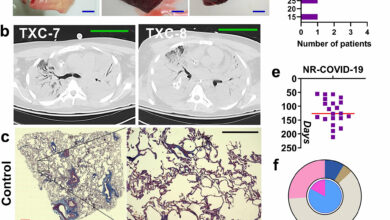

Mulheres com sobrepeso têm maior probabilidade de sofrer de COVID longo, de acordo com nova pesquisa

Crédito: Unsplash/CC0 Public Domain Mulheres com sobrepeso são mais propensas a apresentar sintomas de COVID longo, de acordo com uma…